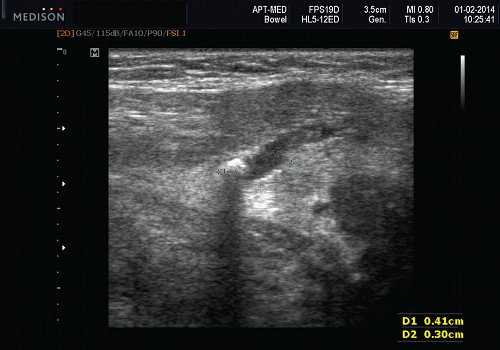

Рис. 5. Камень протока поднижнечелюстной слюнной железы.

Рис. 6. Камень в паренхиме поднижнечелюстной слюнной железы.

Рис. 7. Камень в протоке поднижнечелюстной слюнной железы.